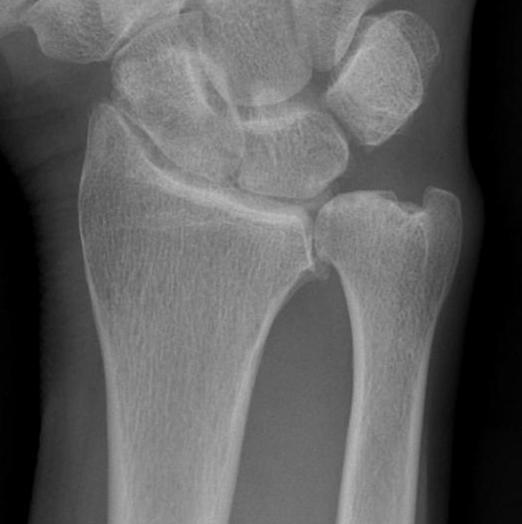

Xray

DRUJ instability

Post traumatic distal ulna osteoarthritis